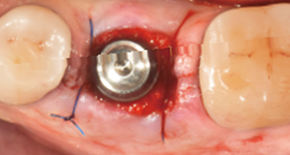

1. Extraction

2. Suture after MagiCore placement

3. Recovery